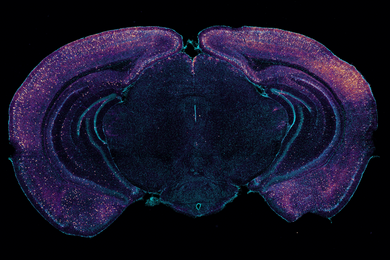

Prof. Ed Boyden and Prof. Li-Huei Tsai have “found that if gamma waves through non-invasive stimulation, were put back into baseline frequency, it could slow down the process in certain brain diseases such as Alzheimer’s,” reports Hansa Bhargava for Forbes